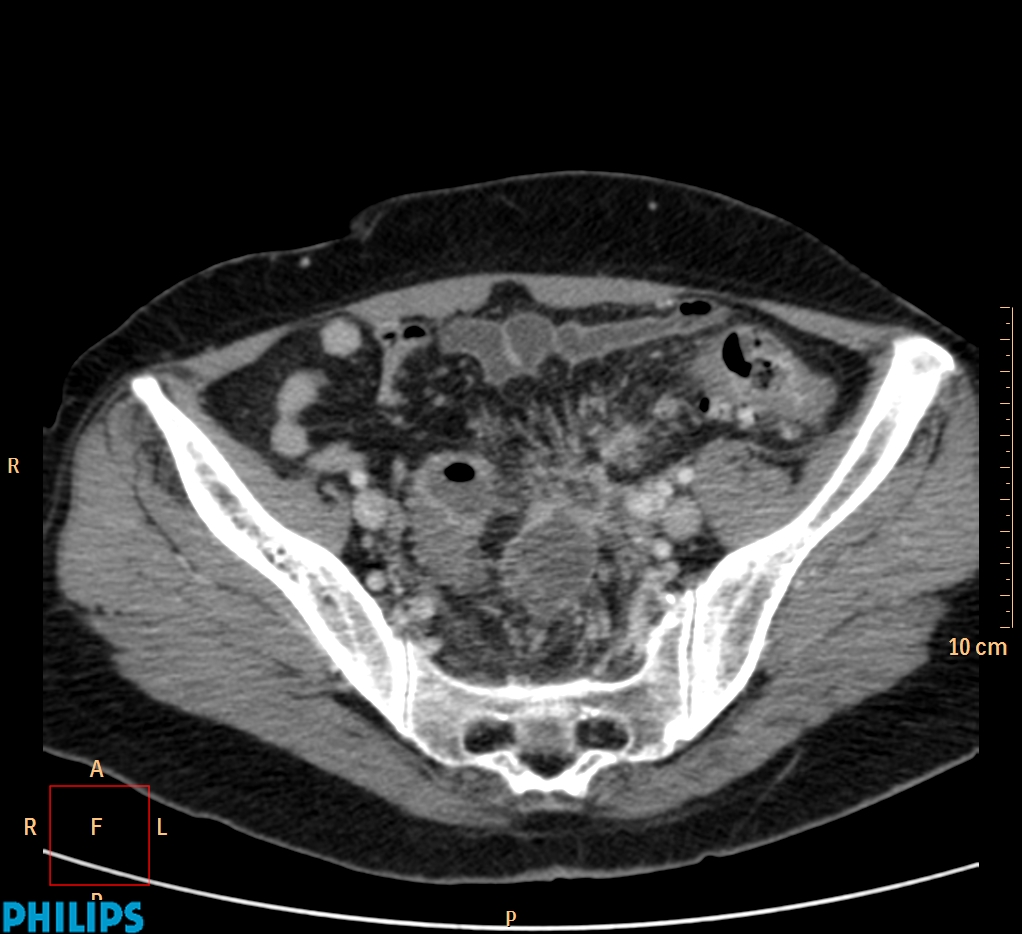

ΕΚΚΟΛΠΩΜΑΤΑ ΠΑΧΕΟΣ ΕΝΤΕΡΟΥ Posted by ΙΠΠΟΚΡΑΤΕΙΟ ΙΩΑΝΝΙΝΩΝ | Dec 16, 2020 | ΠΕΠΤΙΚΟ | 0 ΚΛΙΝΙΚΑ ΣΤΟΙΧΕΙΑ – ΙΣΤΟΡΙΚΟ υποτροπιάζοντες επαναλαμβανόμενοι πυρετοί κυρίως απογευματινές ώρες ΕΡΓΑΣΤΗΡΙΑΚΟΣ ΕΛΕΓΧΟΣ ΑΠΕΙΚΟΝΙΣΤΙΚΟΣ ΕΛΕΓΧΟΣ διακρίνονται τα αποστήματα στην ελάσσονα πύελο, καθώς και εκκολπώματα με εικόνα πάχυνσης του τοιχώματος του σιγμοειδούς ΣΥΖΗΤΗΣΗ